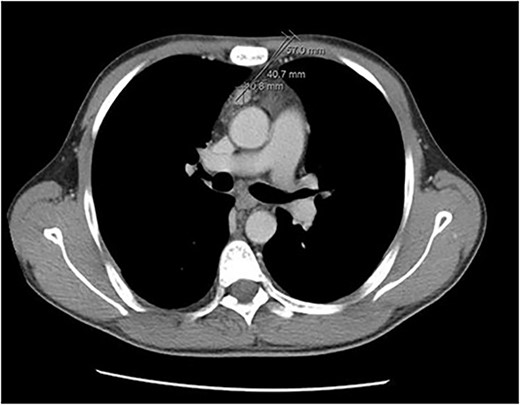

A 36-year-old male with a history of end-stage renal disease (because of polycystic kidney disease) on dialysis, for which he is on paricalcitol and sevelamer, and total parathyroidectomy with autotransplantation in the left forearm performed in 2011 for secondary hyperparathyroidism presented with generalized bone pain. Heart rate was 114 bpm, respiratory rate was 18 breaths/min, oxygen saturation was 96% and blood pressure was 136/72 mmHg. Laboratory investigations were ordered and revealed high PTH (>1300 pg per ml), low calcium (2.7 mg per dl) and low phosphate (1.8 mg per dl). A sestamibi scan was ordered and revealed hyperactive parathyroid tissue in the upper retrosternal area (Fig. 1). Removal of the ectopic parathyroid tissue was planned; however, the lesion was not localizable intraoperatively, and further chest CT with preoperative coil localization was performed, which revealed a retrosternal ectopic parathyroid tissue anterior to the ascending aorta (Fig. 2).Right thoracoscopy using fluoroscopy for ectopic parathyroid removal and lymph node biopsy was performed, and the specimens were sent to histopathology, which showed multiple nodules of parathyroid tissue with benign lymph nodes (Figs 3 and 4). A final diagnosis of parathyromatosis was made. The patient was discharged in good condition without complaints of bone pain. Upon 2-week follow-up, the patient was symptom-free and laboratory investigations revealed phosphate of 2.1 mg per dl, calcium of 2.4 mg per dl and an elevated PTH of 350 pg per ml, for which a sestamibi scan was performed and showed no evidence of uptake in the neck and mediastinum but revealed uptake in the left forearm from the previous autotransplantation.

Chest CT revealing a retrosternal lesion measuring 57 mm anterior to the ascending aorta.